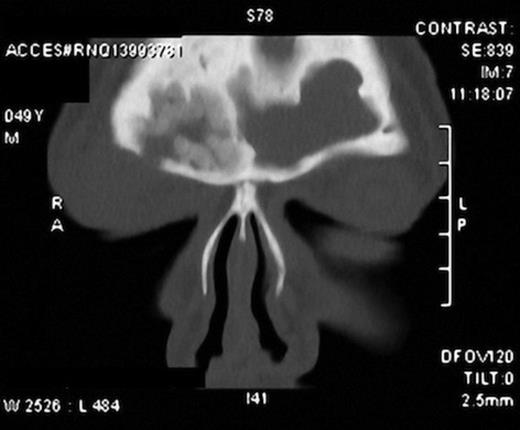

Suspecting a possible retained orbital foreign body, an urgent CT scan was requested. It showed a bony defect in the right superior orbital rim secondary to chronic frontal bone osteitis and chronic inflammatory sinusitis involving frontal and maxillary sinuses bilaterally (Figure 2). Right globe was normal with normal extra ocular muscles, optic nerve and superior ophthalmic vein. In addition, massive thickening of pre septal soft tissues of the right orbit was noticed with no evidence of any retained foreign body.

CT scan showing defect in the right superior orbital rim and periorbital soft tissue swelling. Also seen are the inflamed sinus cavities.